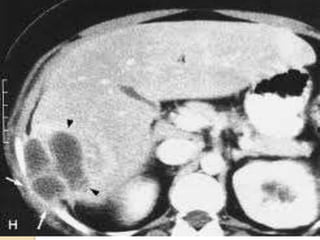

CT ABDOMEN: Mildly enlargedliver with multiple variable sized marginally enhanced cystic lesions are seen scattered in both liver lobes and caudate lobe . the largest measures about 3.5 cm in diameter and located in medial segment of the left liver lobe…… signs cobe with multiple liver granulomas Normal enhancement of the main portal vein and its two main branches. No dilated intra-hepatic biliary

abdominal CT a contrastenhancing multicystic lesions that can be approached by CT guided needle biopsy and C/S